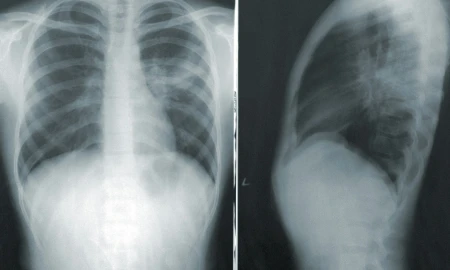

Affections pulmonaires

Les risques connus de fragilité pulmonaire regroupent le tabac, l’âge, les pathologies qui dépriment le système de défense immunitaire. Les maladies pulmonaires peuvent dans ces cas être une bronchite, une pneumonie, un emphysème et une maladie pulmonaire chronique obstructive.

Les parodontites peuvent être un autre facteur de risque de pathologie respiratoire, en présence d’un terrain fragilisé par surinfection d’une lésion pulmonaire existante. Nous savons aujourd’hui que les infections buccales, incluant les parodontites, sont associées à l’augmentation du risque d’infection pulmonaire.